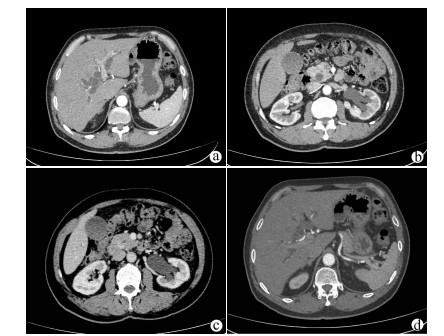

IgG4相关硬化性胆管炎临床特征及诊疗过程分析

李丽, 刘晖, 宋文艳

2021, 37(8): 1883-1887. DOI: 10.3969/j.issn.1001-5256.2021.08.026

摘要(1357) HTML (591) PDF (2114KB)(101)

摘要:

目的  观察IgG4相关硬化性胆管炎临床特点, 并对其诊疗过程进行分析。  方法  回顾性分析2014年1月—2020年9月在首都医科大学附属北京佑安医院诊断为IgG4-SC的25例患者的临床资料,通过电子病例系统采集患者基本信息、病史、诊疗经过、实验室检查、影像、病理资料。分析临床特征、确诊流程、误诊原因等。符合正态分布的计量资料用x ±s表示,非正态分布的计量资料用M(P最小值~P最大值)表示。  结果  25例IgG4-SC患者以男性为多见(21例,84%),平均年龄(57.61±9.73)岁,首发症状常见皮肤黄染和/或尿黄(18例,78.26%)、乏力(9例,39.13%)等。影像学分类:Ⅰ型16例(64%);Ⅱa型0例,Ⅱb型4例(16%);Ⅲ型1例(4%);Ⅳ型4例(16%),合并胰腺受累最多见(22例,88%)。治疗主要以糖皮质激素为主,2周内TBil平均下降67.48%。确诊的22例患者中,门诊拟诊“胆胰系统占位” 15例(68.18%),拟诊“梗阻性黄疸”5例(22.73%)。早期认识IgG4-SC疾病是通过术后病理,随后影像医师逐渐认识,最后通过多学科会诊方式使更多临床医生认识该病,患者得以更早确诊。  结论  对梗阻性黄疸的患者,临床医生需要结合临床表现尤其是影像学特点,对IgG4-SC进行鉴别。影像科、病理科、多学科会诊方式在帮助临床医师认识疾病、确定诊断方面发挥重要作用。